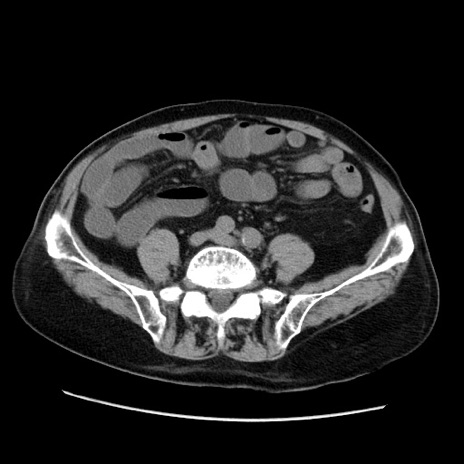

症例21(横断像)

【症例】70歳代男性

【主訴】腹痛

【現病歴】肝硬変・肝細胞癌にてかかりつけの方。約9時間前に食後より腹痛出現。症状が徐々に増悪し、嘔吐出現したため来院。

【既往歴】肝硬変、肝細胞癌(RFA、TACE後)

【身体所見】意識清明、表情苦悶様、BT 36℃、BP 129/78mmHg、P 88bpm、SpO2 97%(RA)、右上腹部から心窩部にかけて圧痛あり、反跳痛なし、筋性防御あり。

【データ】WBC 5800、CRP 0.16